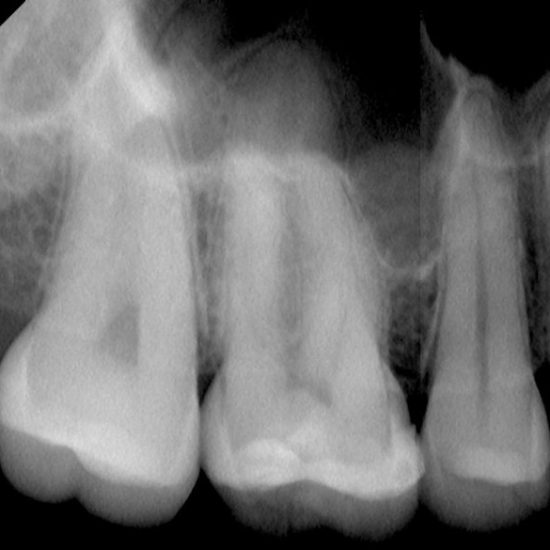

BITEWING SLIKANJE ZOBNIH KRON

Bitewing slikanje zob je tehnika, ki se uporablja za prikaz zobnih kron. Slika je primerna za odkrivanje interdentalnega kariesa(področje kjer se zobje stikajo)

Slikanje zobnih kron (bitewing)

10€